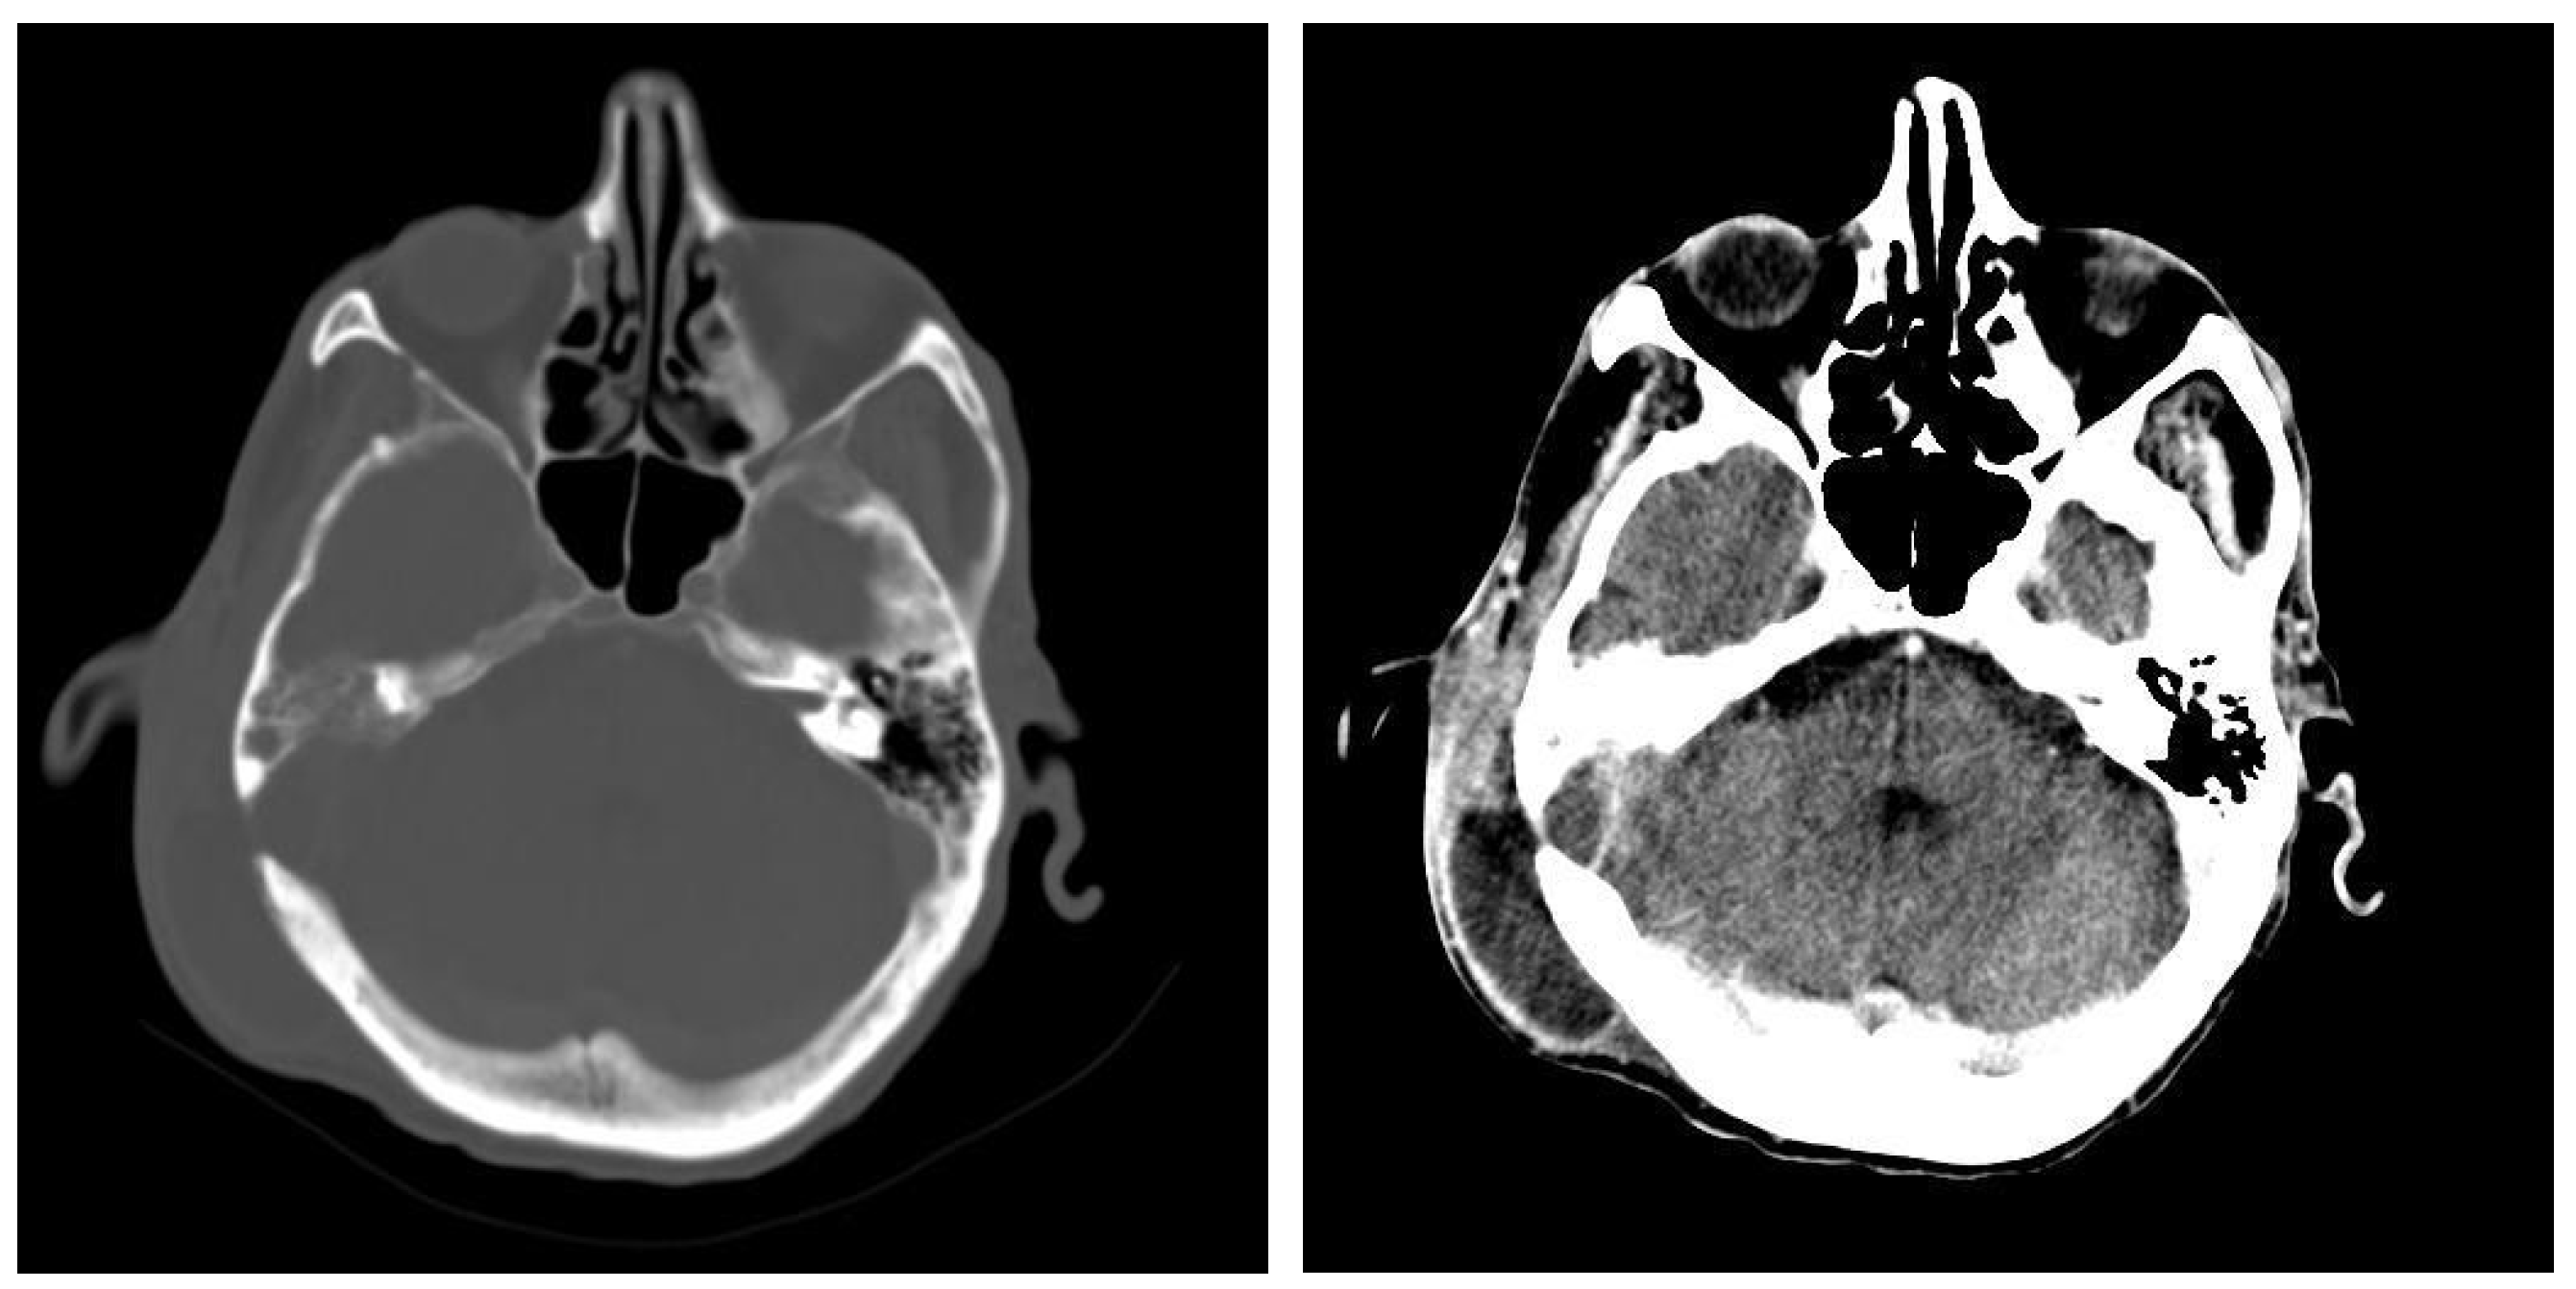

3.1.2. Computed Tomography and Magnetic Resonance Imaging

| CT Aspects | Number of Patients | Percentage |

|---|---|---|

| Fluid accumulation | 168 | 100% |

| Osteolysis | 152 | 90.47% |

| Osteocondensations | 128 | 76.19% |

| Cholesteatoma | 48 | 28.57% |

| Exocranial extensions | 48 | 28.57% |

| Intracranial extensions | 24 | 14.28% |

| Changes to the external auditory canal | 68 | 40.47% |

| Ossicular chain damage | 144 | 85.71% |